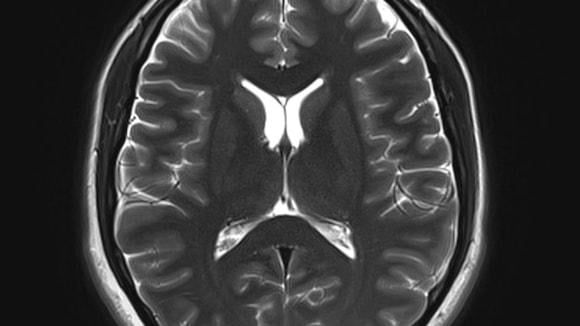

Aug. 26, 2024 — Data scientists and clinical researchers will use brain scans from the entire Scottish population to build a software tool that they hope will help predict a person’s risk of dementia.

The team from the Universities of Edinburgh and Dundee, has approval to use a unique, large data set made up of CT and MRI brain scans from patients in Scotland from 2008 to 2018, representing 1.6 million images.

The team will use artificial intelligence and machine learning to analyze the image data alongside linked health records such as demographics and treatment history, without patients being identifiable, to find patterns that could indicate a person’s risk of developing dementia.

The ultimate aim is to build a digital healthcare tool that radiologists can use when scanning for other conditions to determine a person’s dementia risk, and to diagnose early stages of related diseases, such as Alzheimer’s.